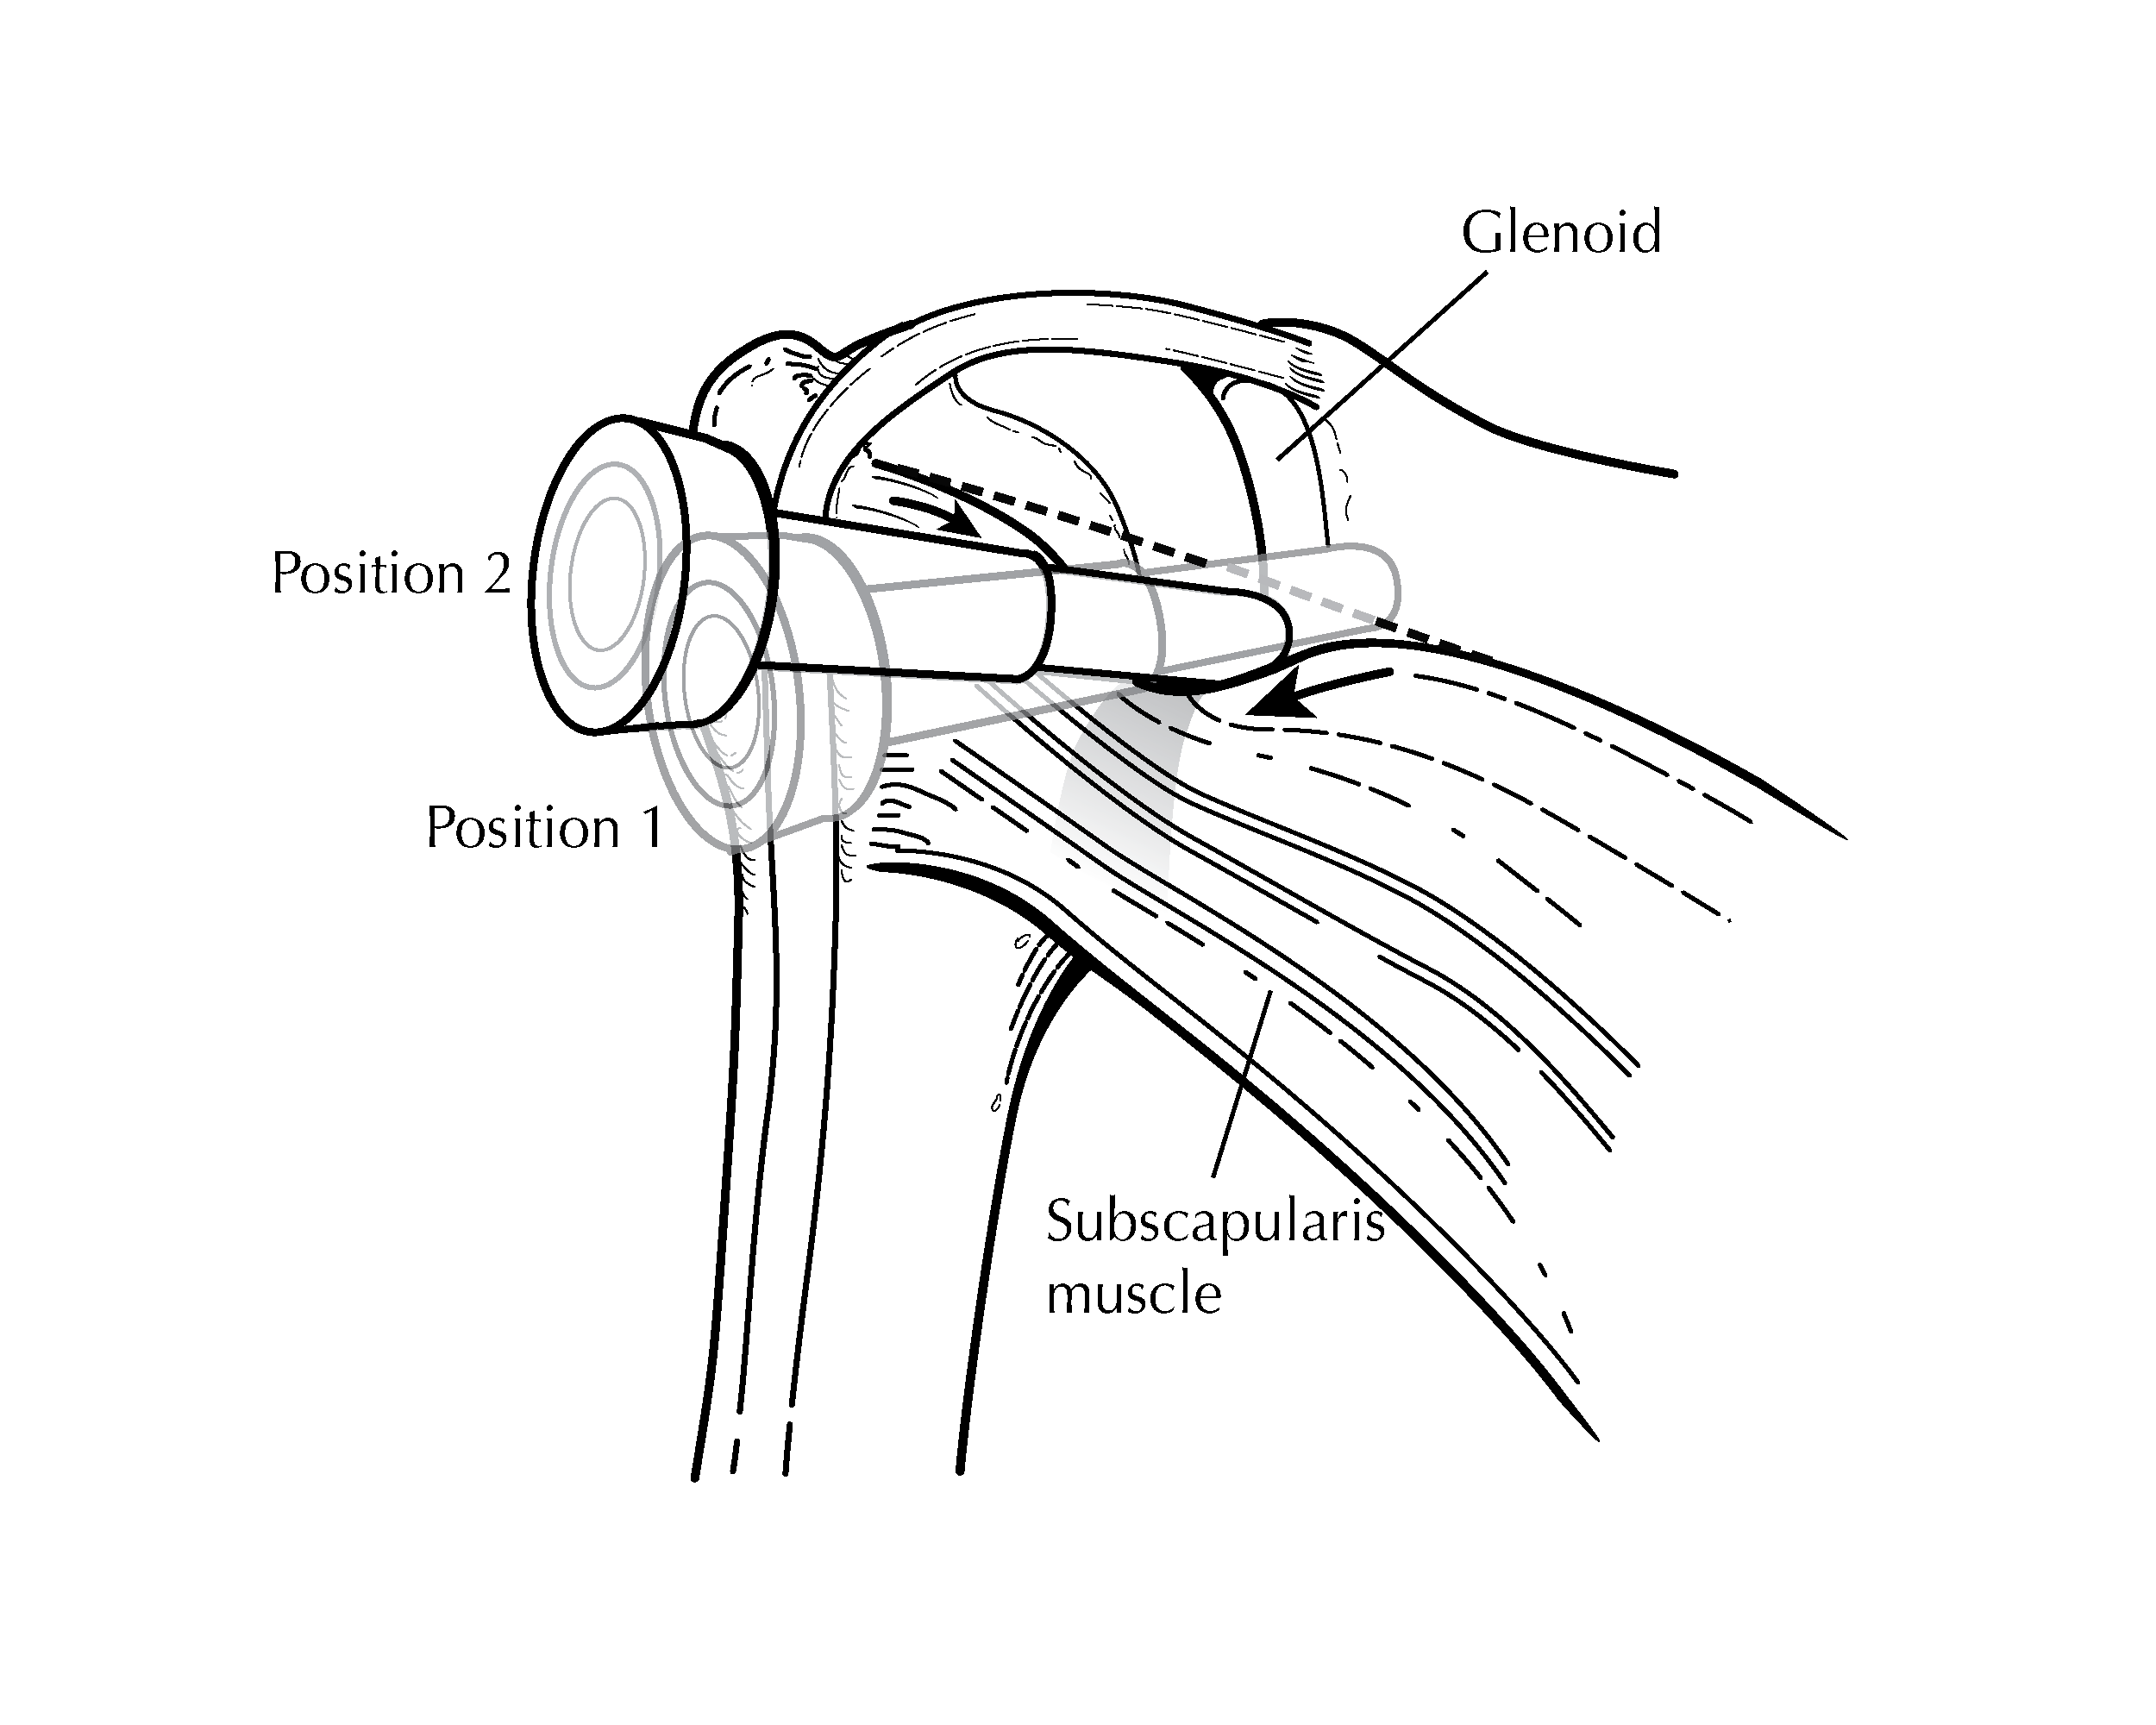

Surgical illustrations visually depict operative techniques, surgical anatomy, and complex procedures. They are created with high anatomical accuracy and serve as a visual bridge between complex surgical knowledge and learners, clinicians, or patients.